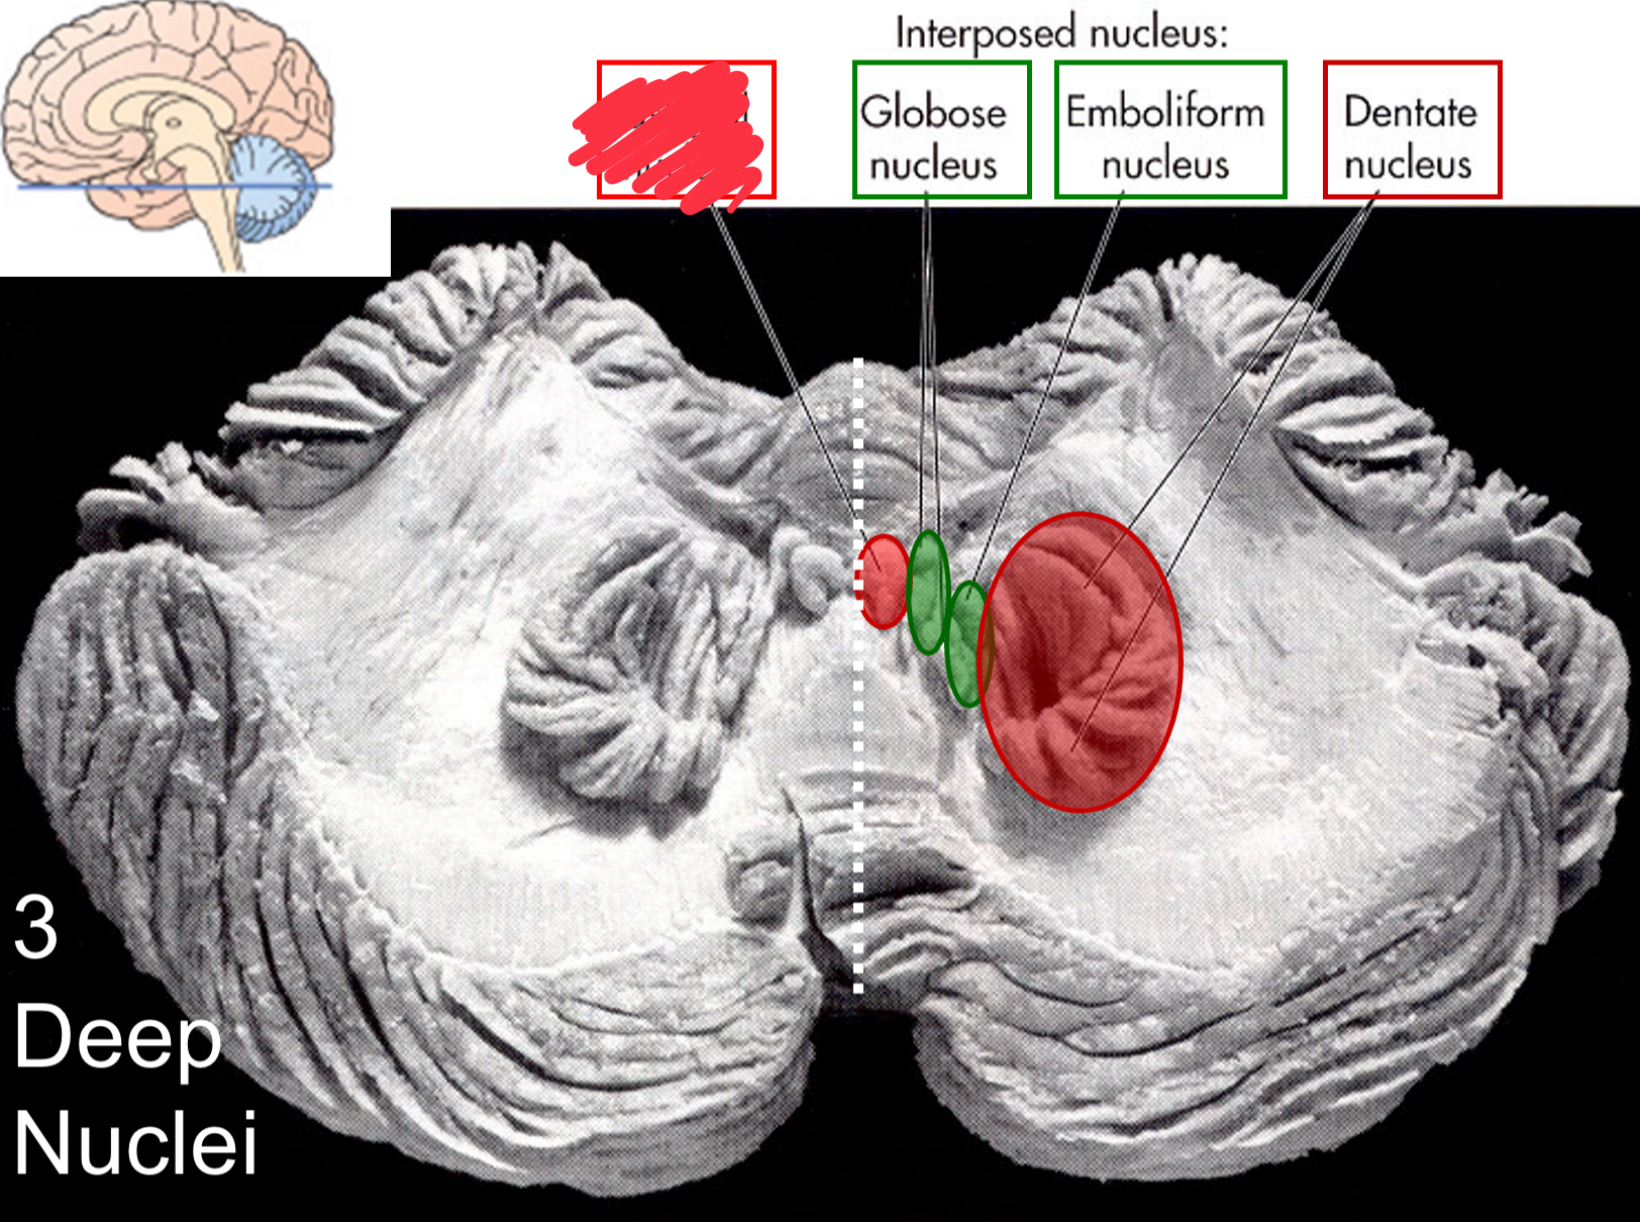

fastigial nucleus

interposed nucleus (globose + emboliform)

dentate nucleus